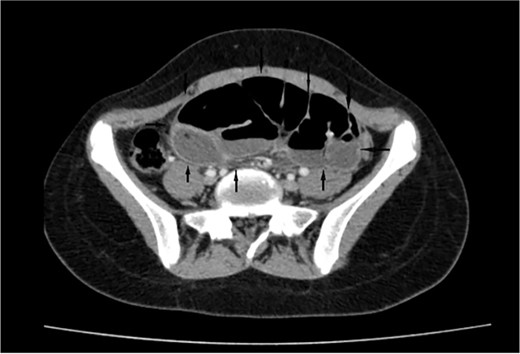

On a retrospective review of our patient’s ECT, we recognised a membrane encapsulating the small intestine centrally, which indicates the diagnosis of ACS (Figs 4 and 5).

Retrospective review of ECT (coronal section), a membrane encapsulates the small intestine centrally indicates the diagnosis of ACS (black arrows).